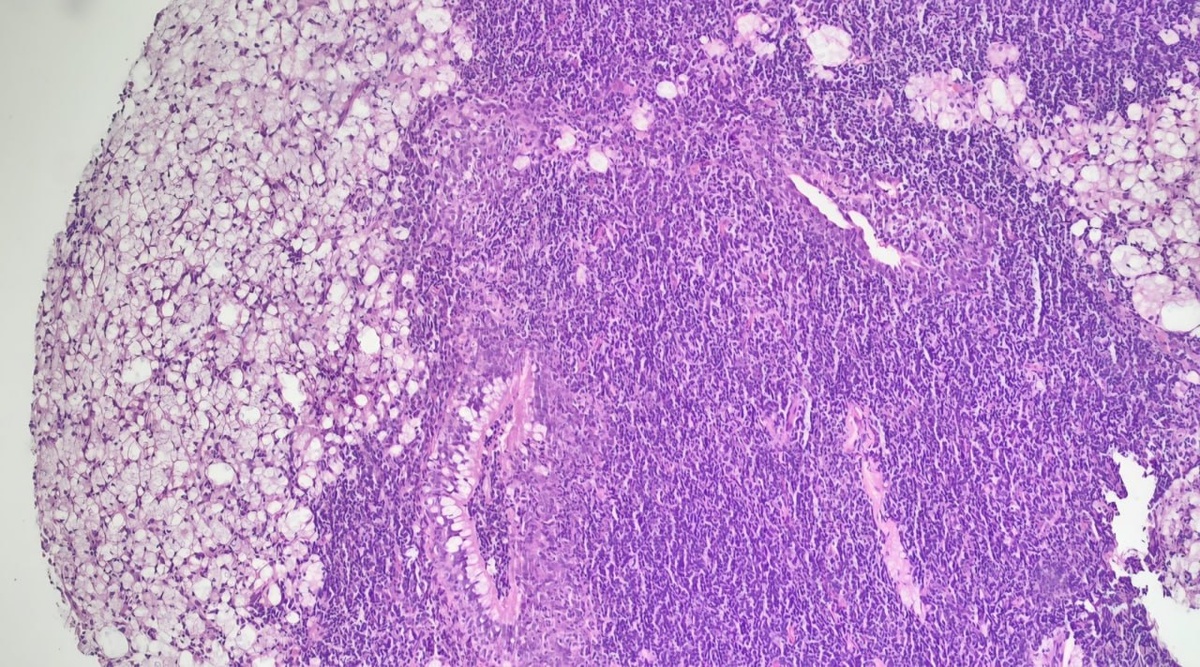

Клинический случай Пациент: мужчина 51 года, ВИЧ-положительный статус Жалобы: шум в ушах (продолжительность — 3 месяца) Данные обследования: * При оториноларингологическом осмотре выявлено: утолщение слизистой оболочки носоглотки * Выполнена биопсия Гистологическое заключение: Криптококкоз носоглотки #cryptococcus #гистология

Пациент: мужчина 51 года, ВИЧ-положительный статус

Жалобы: шум в ушах (продолжительность — 3 месяца)

* При оториноларингологическом осмотре выявлено: утолщение слизистой оболочки носоглотки

* Выполнена биопсия

Гистологическое заключение:

Криптококкоз носоглотки